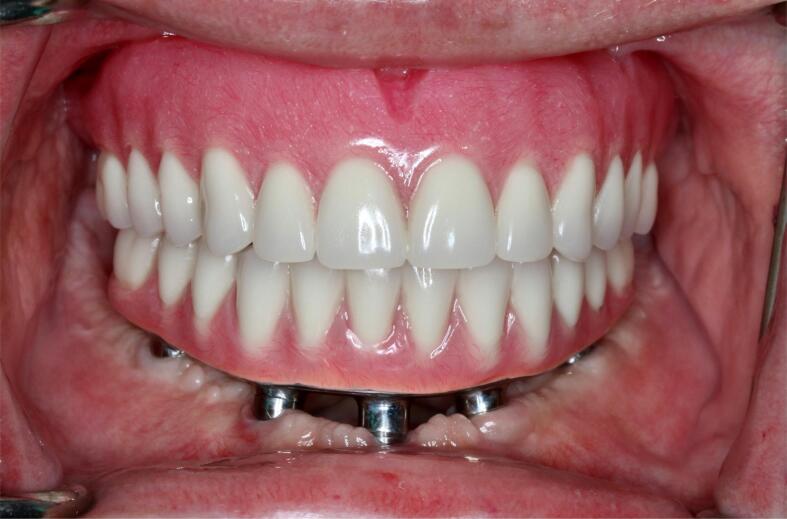

Fig. 6.

Post-treatment intraoral frontal view presenting the definitive prosthesis (mandibular implant-supported fixed dental prosthesis) and (maxillary removable complete denture).